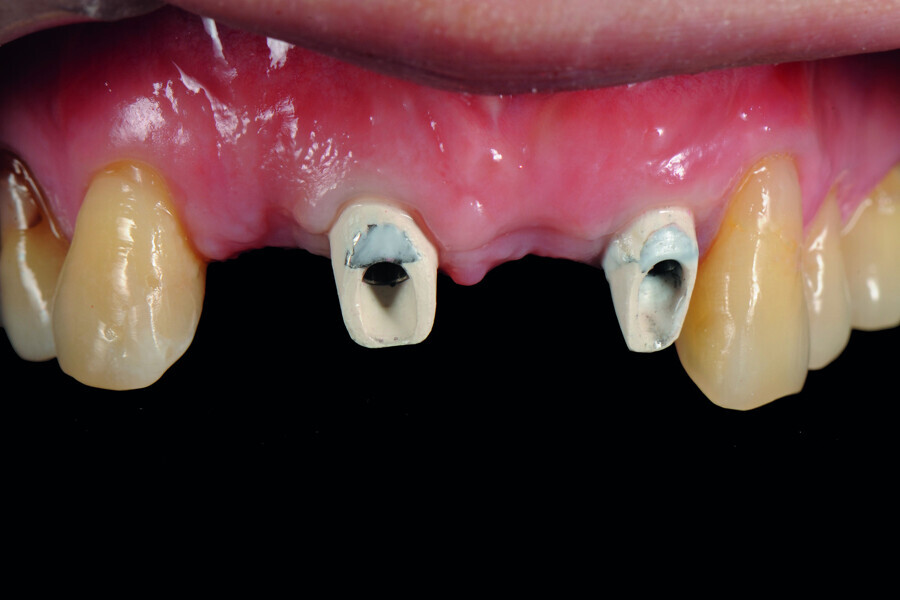

Fig. 5: Frontal view of the anterior teeth immediately post-op.

Fig. 6: Occlusal view of the anterior teeth immediately post-op.